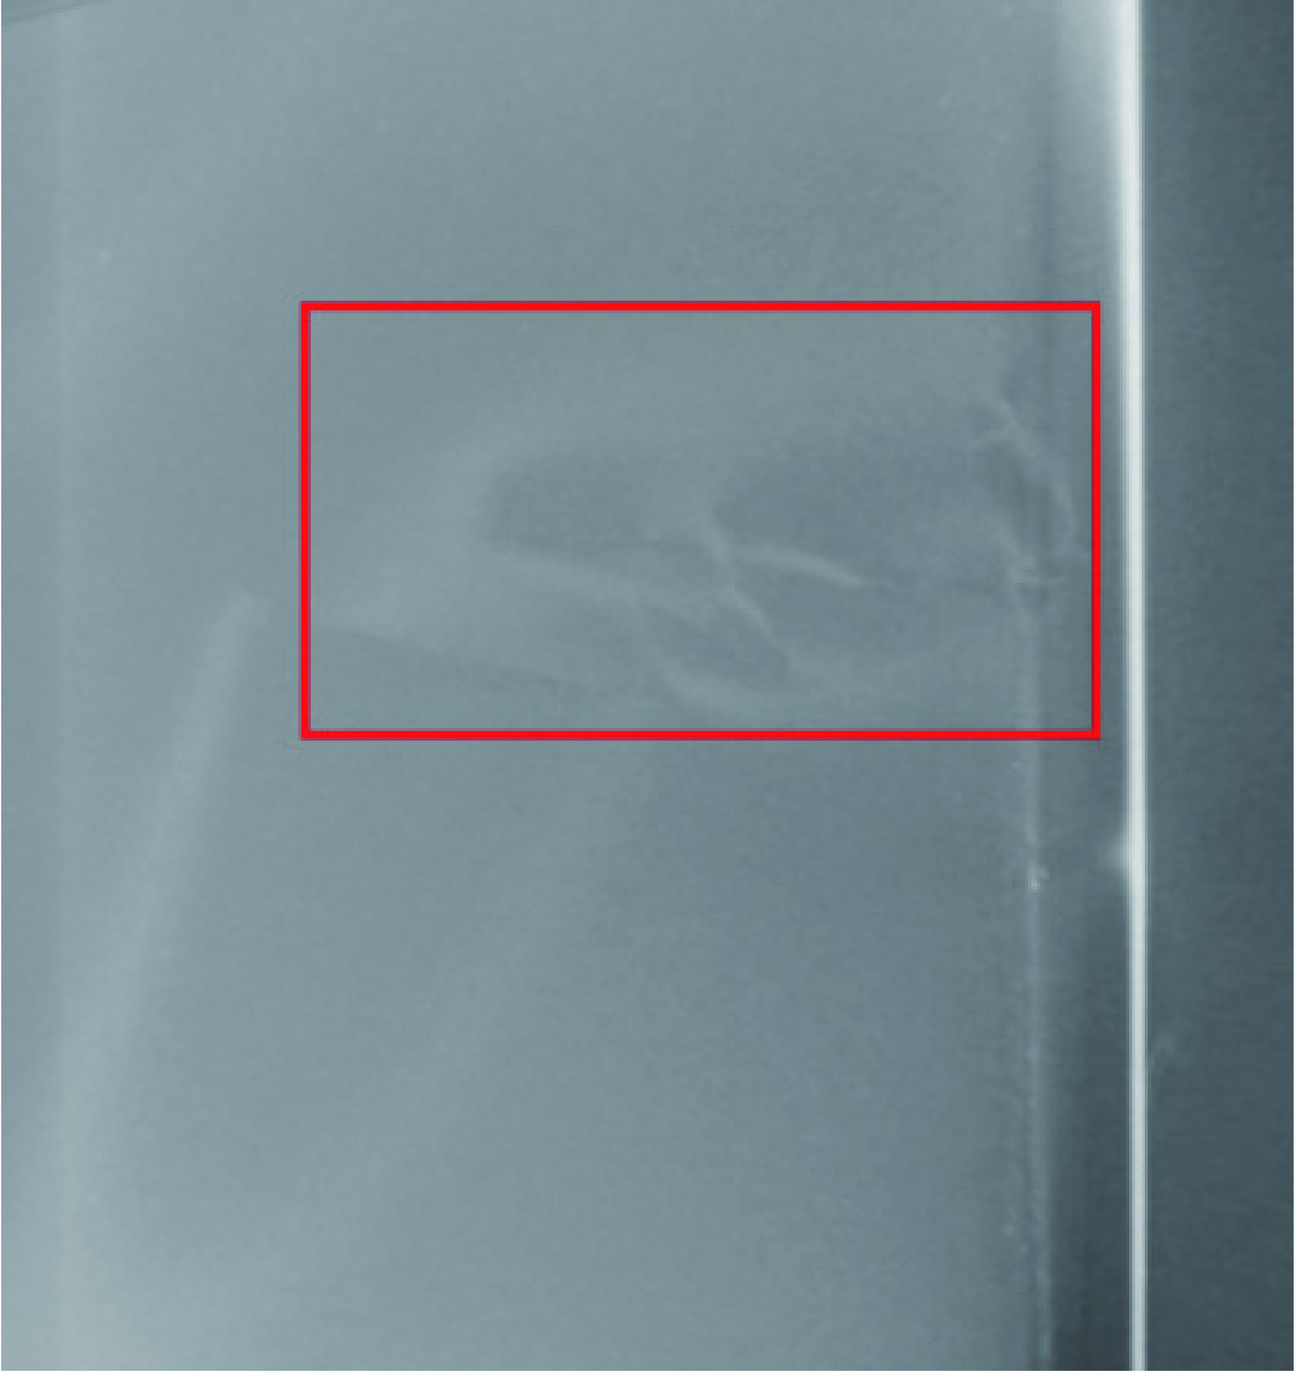

在本实验中,我们特别测量了代表标准肝脏密度(ρew=1.06)的插入物(图1箭头指示)。在整个扫描过程中,体模的位置始终保持固定不变。

使用一台256排CT(Revolution CT,GE医疗)完成体模扫描工作(图1)。在进行扫描时,参照腹部诊断CT扫描参数设置(表1),将管电压设定为120 kVp[15],并根据需要调整管电流,以产生6种不同的辐射剂量(容积CT剂量指数(volume CT dose index(CTDIvol):30、20、15、10、7.5和4.5 mGy)。其中,以15 mGy的剂量为标准的腹部扫描剂量[13]。重建图像的层厚和层距都是1.25 mm,重建图像视野为30 cm×30 cm,图像重建矩阵为512×512。